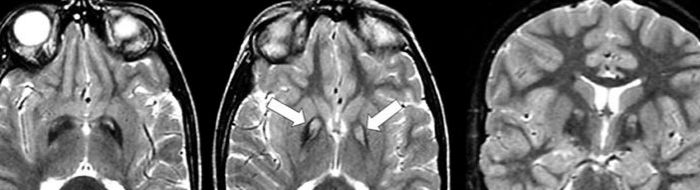

- Central nervous system: cognition, neurodegeneration and mood disorders